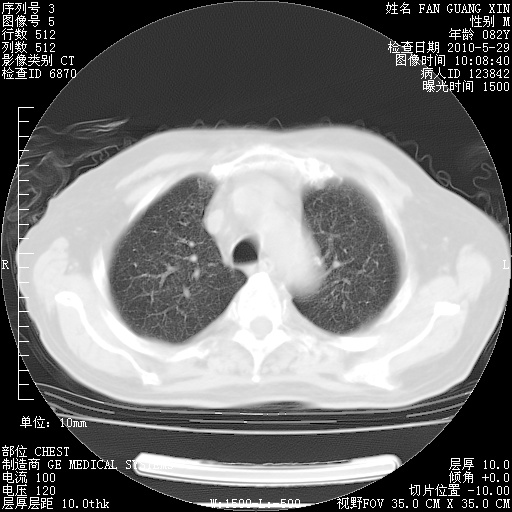

再治疗10天后的肺部CT

阅读此次胸部CT,肺间质渗出性改变较入院时有吸收。目前从体温、白细胞、中性分叶明显增高,肯定存在细菌感染(发生医院感染哦,若无消化道及泌尿系统等感染的依据,肺部感染可能大)。若你院头孢哌酮舒巴坦钠耐药率较高,同意你的方案,若48小时体温仍高,可考虑使用碳青霉稀类抗菌药物,同时可予超声雾化、注意滴数时加大液体量。白蛋白33.30g/L较低哦,需加强营养等支持治疗。

从白细胞总数和中性比例看好像合并感染。肺部纹理好像比上次多,支气管炎?其他感染?